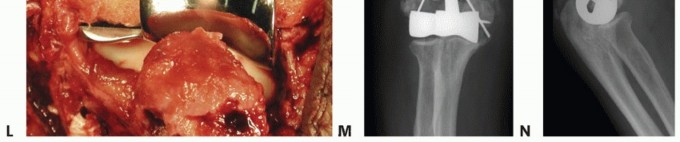

During a distal humeral hemiarthroplasty (DHH), the bony preparation is focused on the medial and lateral columns. When these are not intact, reconstruction with temporary K-wire fixation to judge length and more definitively either wire or tension band fixation or plate and screw fixation should be attempted (TECH FIG 4I-N). The preservation and reconstruction of the columns are especially important when using an implant without an anterior flange.

TECH FIG 4 • (continued) I-K. Latitude DHH. I. Intact medial and lateral humeral columns, with a red vessel loop loosely around the ulna nerve. J. AP radiograph demonstrating the trochlea and capitellum correctly sized for the host, greater sigmoid notch of the ulna, and the radial head. K. Lateral radiograph demonstrating a well-aligned radio capitellar joint and osseous integration of the anterior flange. L-N. Sorbie DHH. L. Fractured medial and lateral columns were reconstructed with K-wires, prior to implant insertion. M. AP radiograph demonstrating a well-seated Sorbie implant with healed medial and lateral columns. N. Lateral radiograph demonstrating a well-aligned radiocapitellar joint with posterior heterotopic ossification in the traumatically injured triceps muscle.